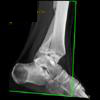

Clinical History: 12 year old female who fell down steps. She presents with left lower extremity pain.

CT Findings: Nondisplaced triplane left ankle fracture involving medial malleolus, with opened epiphysis.

Diagnosis: Minimally displaced of the medial malleolus and widening of the epiphyseal plate defined.

Outcome: Nonweightbearing. She was placed in a splint.